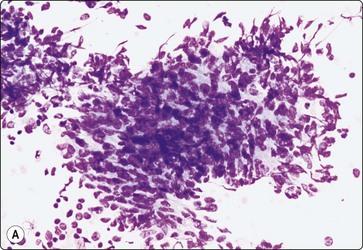

Kaposi’s sarcoma

This neoplasm is caused by human herpesvirus-8 and is derived from infected endothelial cells. It is an AIDS-defining illness and one of the commonest neoplasms seen in homosexual AIDS patients, although in the HAART era, its incidence has decreased and been overtaken by lymphomas and squamous mucosal lesions. In lymph nodes, the spindle cell proliferation involves the subcapsular and other sinuses, and the remaining lymph node shows the various stages of HIV infection, from follicular hyperplasia through to involution. Nodal involvement should be considered in patients with tender lymphadenopathy, low CD3 count, associated infections and Kaposi’s sarcoma skin lesions.70

Criteria for diagnosis (Fig. 18.17)

Low cell yield; irregular tissue fragments of haphazardly arranged spindle cells,

Elongated, blunt-ended, mildly irregular hyperchromatic nuclei with inconspicuous nucleoli,

Poorly defined cytoplasm, which in some cases in the Giemsa stain is delineated by metachromatic stroma between the cells,

Single spindle cells with bipolar or long and wispy cytoplasm,

Plasmacytoid lymphocytes, plasma cells, lymphocytes and plentiful tingible-body macrophages.

image image image

Fig. 18.17 (A) Tissue fragment of Kaposi’s sarcoma, showing crowded, spindle shaped cells with hyperchromatic, blunt-ended nuclei (Giemsa, x200); (B) Tissue fragment of spindle cells, with poorly defined cytoplasm Giemsa, x400); (C) Single spindle cells with cigar-shaped bland nuclei, and granular chromatin (Pap, x400) Kaposi’s sarcoma.

Problems and differential diagnosis

The tissue fragments may resemble granulomas, but the nuclei are more elongated and spindly and usually are hyperchromatic. They lack the ‘sand shoe’ indentations of epithelioid histiocytes, and MNGC are not seen. Mycobacterial infection may involve the same node. Occasionally, Kaposi’s sarcoma produces highly cellular smears with large tissue fragments containing slit-like spaces and hemosiderin. Mitoses are scant.